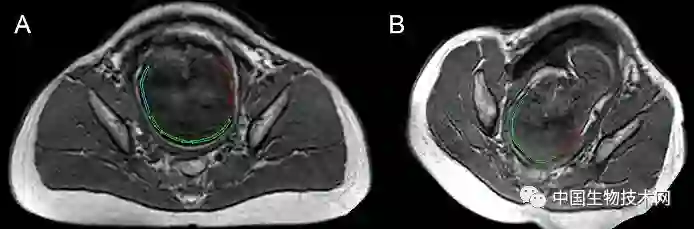

胎头成型和第二产程期间的头部形状变化 图片来源:《PLOS ONE》

近日,法国克莱蒙奥弗涅大学的研究人员利用三维磁共振成像(MRI)技术,拍摄了显示胎儿大脑和头骨在分娩前通过产道时如何改变形状的三维图像。该研究结果近日已发表在《PLOS ONE》上。

众所周知,胎儿头部在出生时是会发生形状改变的,这些变化被称为“胎头成型”,发生在分娩的第二阶段(第二产程)——当胎儿离开子宫通过产道时经历这些变化。然而,研究人员对胎头成型的细节仍知之甚少,只有一项先前的研究曾捕捉到这一过程的图像。

在这项新研究中,为了证明和描述胎头成型和分娩过程中大脑形状的变化,Olivier Ami博士领导的研究团队使用三维MRI捕捉了7名胎儿在分娩前和第二产程中头骨和大脑的详细图像。该分析揭示了所有7名胎儿在第二产程都有胎头成型,其中颅骨的不同部位存在不同程度地重叠。其中5名新生儿的头骨和大脑形状恢复到出生前的状态,但另外2名新生儿的头骨和大脑形状仍在变化。胎头成型程度最高的三名新生儿中有两名是通过紧急剖腹产手术分娩的,另一个是通过阴道分娩的。